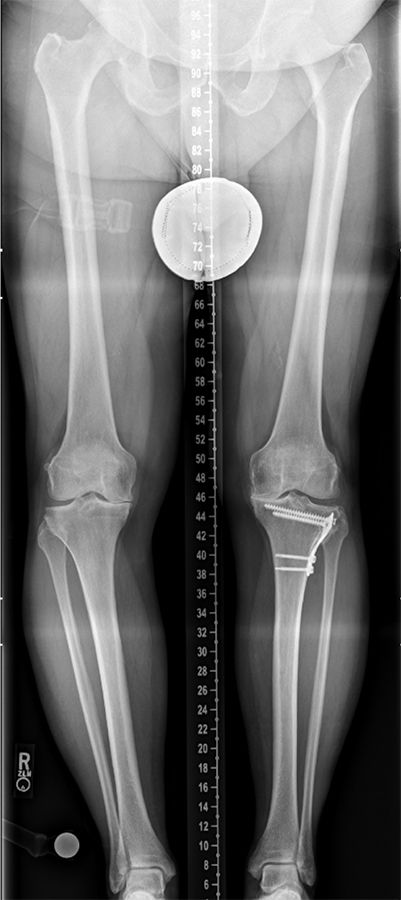

Extraarticular deformities as a result of a femur or tibia fracture usually initiate the development of osteoarthritis through malalignment of the knee. Since they usually are not associated with direct knee injuries the range of motion and overall stability of the knee resembles the clinical picture of primary osteoarthritis of the knee. However, its surgical correction is much more complex since normal alignment of the knee can usually only be achieved in a one stage total knee replacement if either the extraarticular deformity is corrected via a corrective osteotomy at the time of surgery or the extraarticular deformity is corrected through intraarticular soft tissue balancing [1]. In this group of patients, the most challenging clinical question is whether an extraarticular corrective osteotomy is needed prior to joint replacement. Careful planning considering the extend of the coronal deformity on hip to ankle standing views and extend of rotational deformity of the femur are required to make this decision. In addition rotational deformities need to be recognized and might require axial CT or MRI imaging to guide correction.

Osteoarthritis in patients with extraarticular deformities

A hip-to-ankle standing view should be routine for the planning of any total knee arthroplasty. Extraarticular deformities after femur or tibia fractures are frequently overlooked at the time of surgery if the surgeon relies solely on the standard 3 views of the knee itself. In addition, lateral views of the entire femur and tibia can help to asses sagittal deformities once a femur or tibia fracture is identified on hip to ankle views. Rotational CT scan imaging can be considered to analyze rotational deformities especially in patients with fractures of the femur.

To make the decision, whether to correct the coronal deformity in a one stage or two stage fashion or to proceed with a primary total knee replacement the amount of angular deformity at the level of the knee provides the most reliable guidance. No matter where the extraarticular deformity is located doe the purpose of knee arthroplasty the overall mechanical deformity is measured as an angle between the mechanical axis of the femur (line through the center of the hip and the center of the distal femoral condyles) and the mechanical axis of the tibia (line through the center of the talus (ankle) and the center of the tibial plateau). A mechanical deformity in excess of 20-25 degrees usually suggests that a primary knee replacement without deformity correction is not possible. In these cases usually the deformity needs to be corrected first. For the correction of extraarticular deformities different options including correction over a nail, open osteotomy with plate fixation or external fixator exist. In my opinion the technique that interferes the least with the later total knee replacement should be favored. Open ostoeotomies and plate fixation should take into consideration the potential need for hardware removal at the time of surgery and plates should be placed medial along the standard medial parapatellar approach as often as possible. Correction using an intramedullary nail need to make sure that the nail does not extend into the bed of the primary knee implants and options for extramedullary alignment need to be available at the time of total knee arthroplasty (navigation, robotic or extramedullary alignment jigs) [3]. Finally, when using an external fixator, the risk of pin tract infection and osteomyelitis needs to be carefully weighed versus the ability for advanced 3-dimensional correction of the deformity. I personally had very good results with 2 stage correction using an external fixator or one stage correction using either an open plate fixation or intramedullary fixation using the stem of a revision femoral or tibial component. The later is especially appealing if the center of rotation and angulation (CORA) is close to the knee. Bony correction of the preexisting deformity renders the soft tissue balancing at the time of total knee replacement much easier and is usually indicated for less experienced surgeons. Rule of Thumb: For me a coronal deformity exceeding 25 degrees is an absolute and a deformity exceeding 20 degrees is a relative indication for a one stage or two stage correction of a preexisting extraarticular deformity (Figure 1a, b, c).